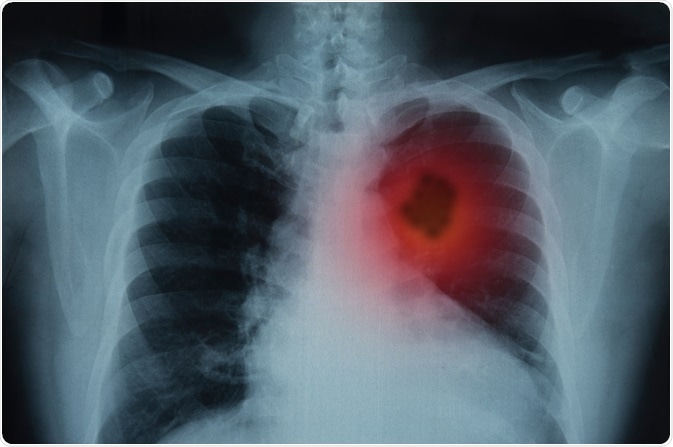

Lung cancer is the most common and deadly cancer, accounting for about 1.76 million deaths globally. Molecular and histological profiling of lung cancer is important to identify molecular and genetic targets for personalized medicine.

Image Credit: create jobs 51/Shutterstock.com